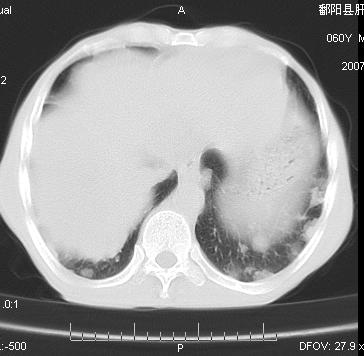

两肺示有散在大小不等类园形边缘不整密增高影.

两肺及胸膜多发性转移瘤。纵隔淋巴结转移.

双侧胸壁见多发结节软组织密度灶,两肺内见广泛结节状、面团样影,两肺及胸膜多发性转移瘤。支持

考虑肝癌双肺转移!腹部强化确诊吧。

根据:病变确实是多发,但大部分边缘不光滑,欠规整,密度不均匀。也就是说“大部分病灶不是典型转移瘤的表现”。转移瘤可以不典型,但如此大部分不典型,却是很少见的。结合发烧病史,考虑肺多发小脓肿或其他炎性病变,如霉菌等感染!建议痰培养,抗炎治疗后复查!